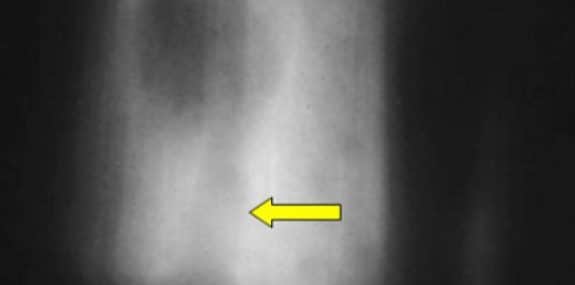

Xray 198 – Global approach to bone lesions

Join Jan Martensen, DC, DACBR for a 1-hour audiovisual course on bone lesions.